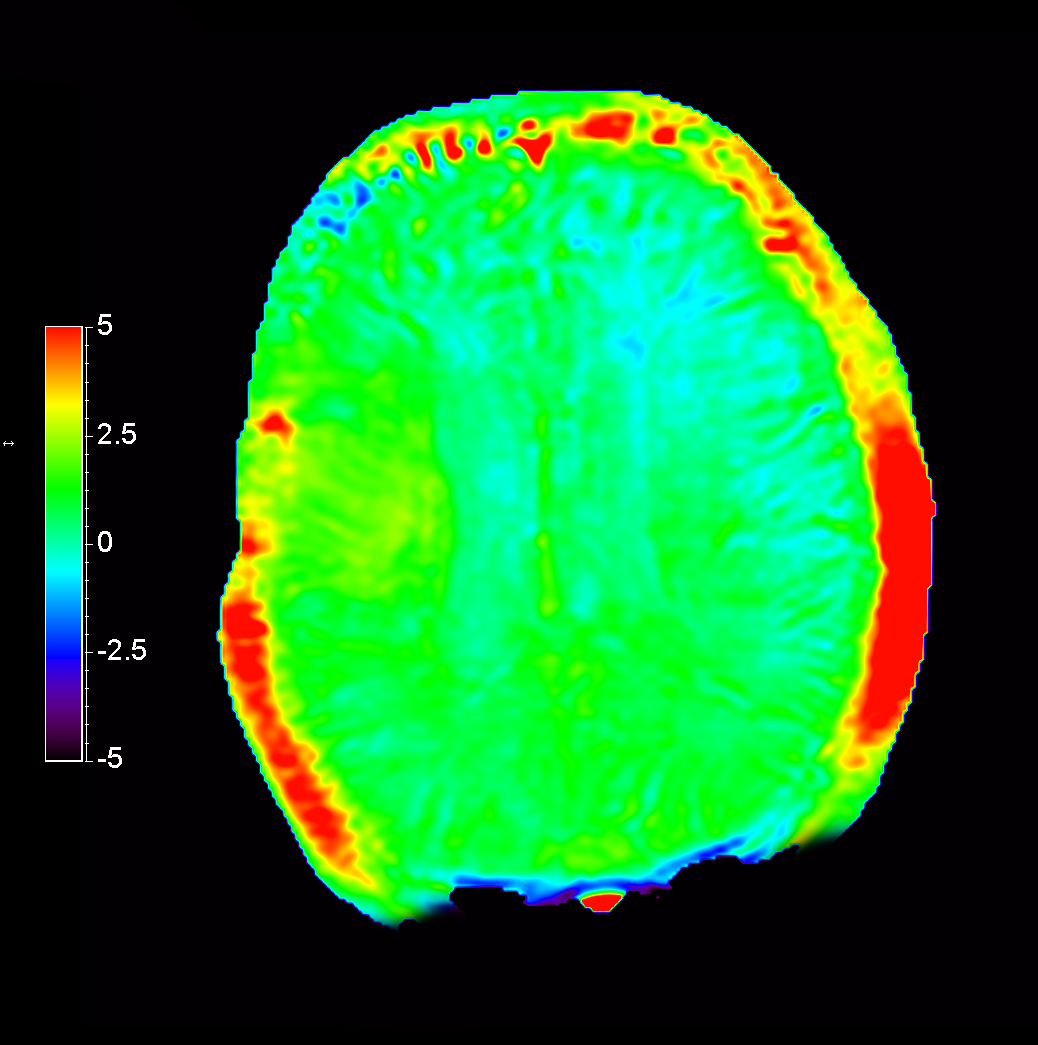

Axial T2* Perfusion - rCBF